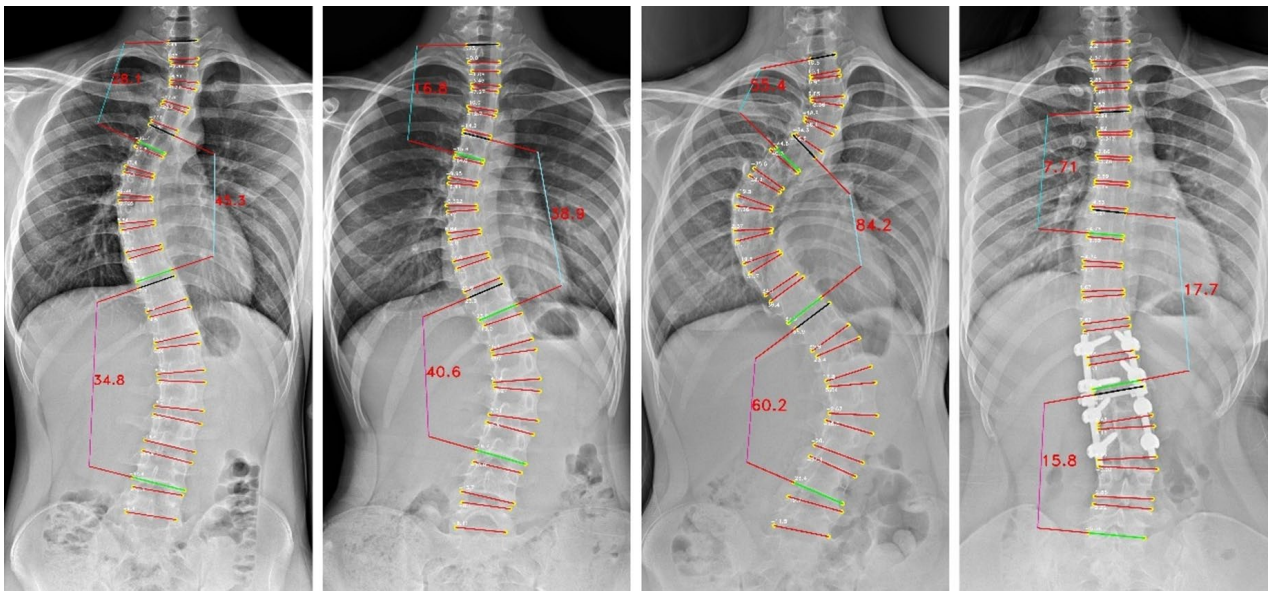

Cobb角是评估脊柱侧弯程度的"金标准",其测量结果可以用于评估病情、制定治疗计划和跟踪疾病进展。万东Cobb角自动测量系统,1秒内即可完成Cobb角计算,较传统手工测量(耗时>2 分钟)效率提升百倍。经研究验证,Cobb角平均测量误差仅3.918°,ICC为0.943,验证了该算法技术指标顶尖、误差小、重复性极好,相关论文收录于脊柱外科和脊柱研究领域的国际顶级期刊之一《European Spine Journal》。

The Pearson correlation only on major Cobb angle of AP view images

The vertebrae four corner points and the Cobb angles measurement for AP view images

The vertebrae four corner points and the Cobb angles measurement for LAT view images

基于负重位CBCT的全脊柱三维Cobb角自动测量,实现了椎体的高精度自动分割,其Dice系数达0.9776(自动分割的结果越准确,Dice值就越接近1),误差极小;三维Cobb角测量可接受度>97.05%,关键椎体识别准确率98.53%,显著优于传统方法。基于负重位CBCT椎体轴向旋转角度自动测量,与人工测量一致性ICC 达0.76,误差控制在±3.04° 内,实现了对椎体旋转的客观、高效、可重复测量,一键自动生成,高效助力临床精准诊疗。该研究入选中华医学会放射学学术大会(CCR 2025)。